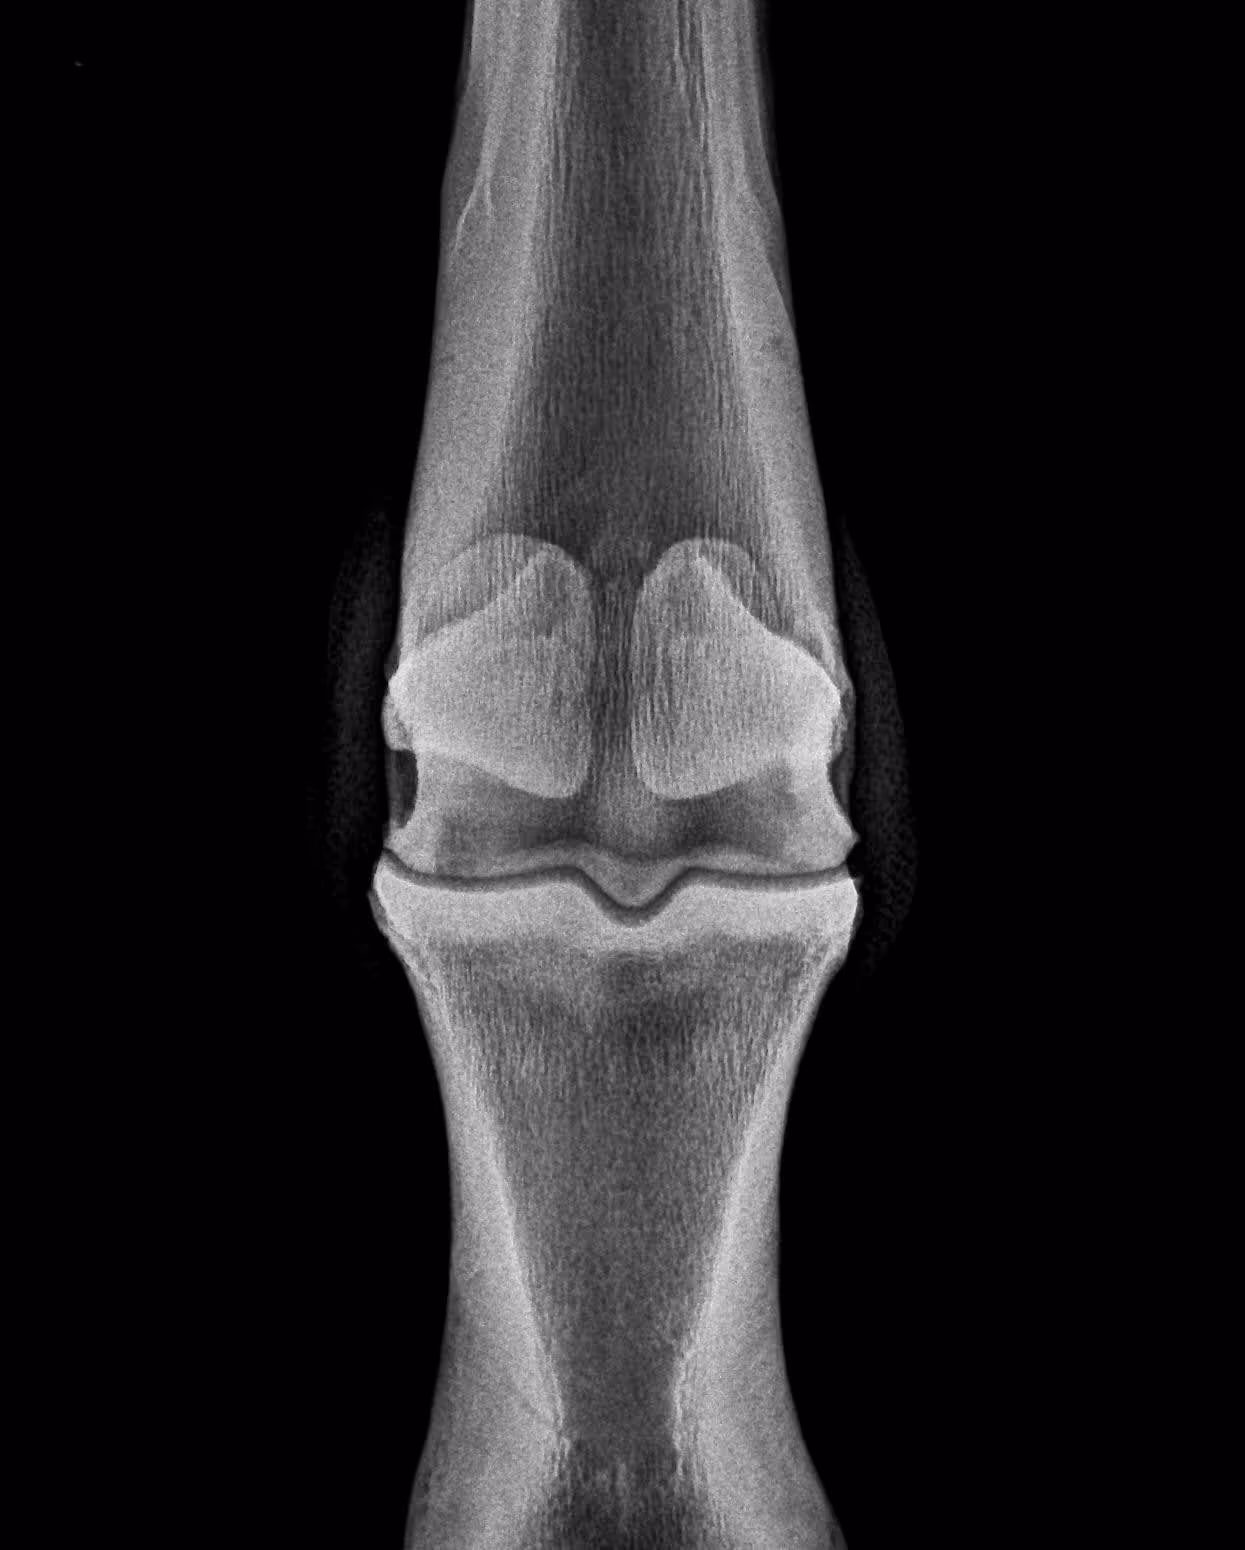

LF fetlock (LM, DLPMO, DP, DMPLO views below):

Moderate arthritis is visible as periarticular bone spurs on medial and lateral margins of P1 and MCIII. A subchondral cystic lesion is present in the medial condyle of MCIII with about 5-8mm of lost subchondral bone width. Periarticular new bone is evident at joint capsule insertions dorsally above and below the joint. Soft tissue swelling is also evident.

DP (dorsopalmar) view. Lateral is to the right. A radiolucency is evident in the medial condyle of MCIII, extending through the subchondral plate; this is a subchondral cystic lesion.